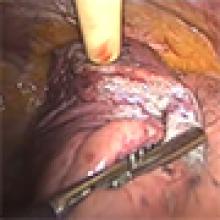

This video describes a method for nodule localization that involves the injection of a technetium (Tc) radiotracer in or near the small lung nodule. A dedicated radioprobe (RMD Instruments, LLC, 44 Hunt St, Watertown, MA) with a 30-degree angled tip provides intra-operative guidance and localization of the preplaced, image-guided radiotracer marker. The described technique provides a reliable tissue diagnosis in 95% of patients and can be used to prevent thoracotomy in 50% of patients with benign disease (1,2).